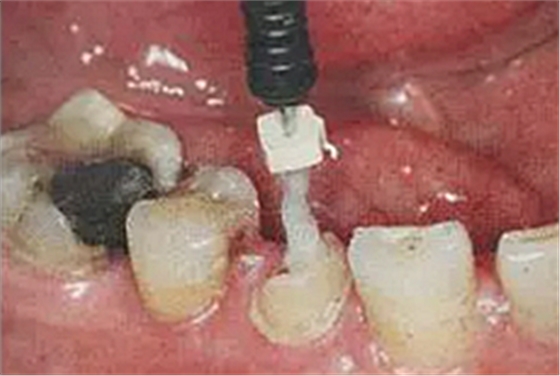

8. 酸蝕和根管內(nèi)酸蝕劑的去除

使用全酸蝕粘接系統(tǒng)粘接纖維樁時(shí),用磷酸凝膠對(duì)根管進(jìn)行酸蝕處理,然后再徹底沖洗干凈,根管內(nèi)酸蝕劑殘留的發(fā)生容易被忽視,這也是影響纖維樁粘接的重要因素之一。

單純的使用三用槍即使反復(fù)沖洗液難將根管內(nèi)的酸蝕劑沖洗盡,尤其是后牙根管。

(冠部及根管全酸蝕)

(三用槍沖洗)

(注射器沖洗)

(根管毛刷清洗)

臨床建議用注射器、三用槍和柱狀毛刷,三者聯(lián)合反復(fù)沖洗。如再配合超聲波振蕩沖洗更佳。